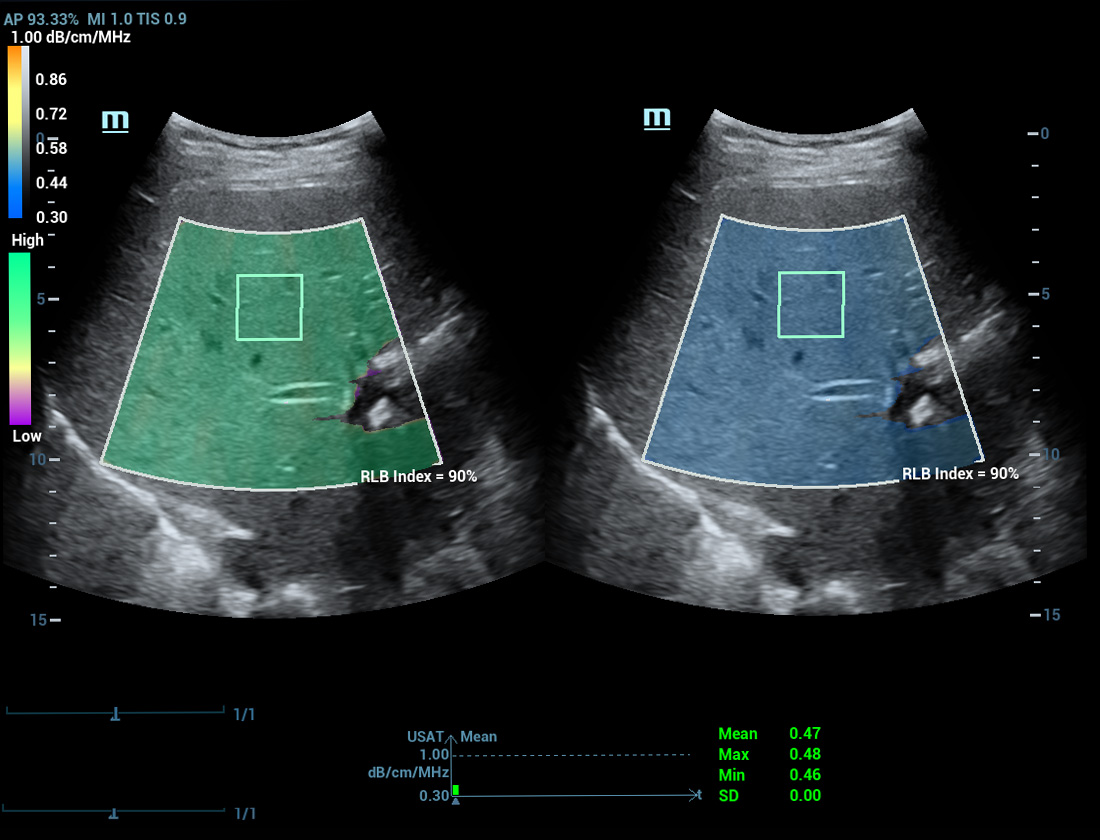

Analisi di laboratorio multiparametriche del fegato grasso

Le analisi di laboratorio multiparametriche del fegato grasso forniscono molteplici strumenti di analisi quantitativa basati su diverse tecnologie acustiche. Consentono di effettuare l'analisi quantitativa della steatosi e migliorano la sensibilitĂ della rilevazione del fegato grasso in fase precoce.

USAT S0